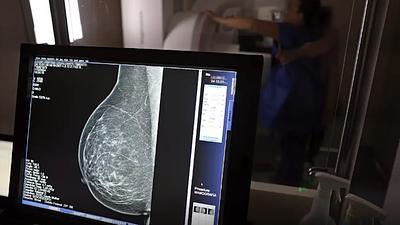

Pesquisa em larga escala aplica IA para detectar câncer de mama

A ferramenta de IA foi aplicada em tempo real e envolvendo um grupo ampliado de pessoas, em vez de ser utilizada posteriormente como vinha sendo feito até agora.

Super Centro usa IA em diagnósticos de câncer de mama

Os laudos dos exames de mamografia realizados no Centro Carioca de Diagnóstico e Tratamento por Imagem (CCDTI) são avaliados e assinados por profissionais médicos capacitados, no entanto, a IA auxilia na identificação de possíveis lesões difíceis de serem vistas.